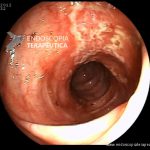

Colite por Doença de Crohn

- Doença de Crohn em atividade